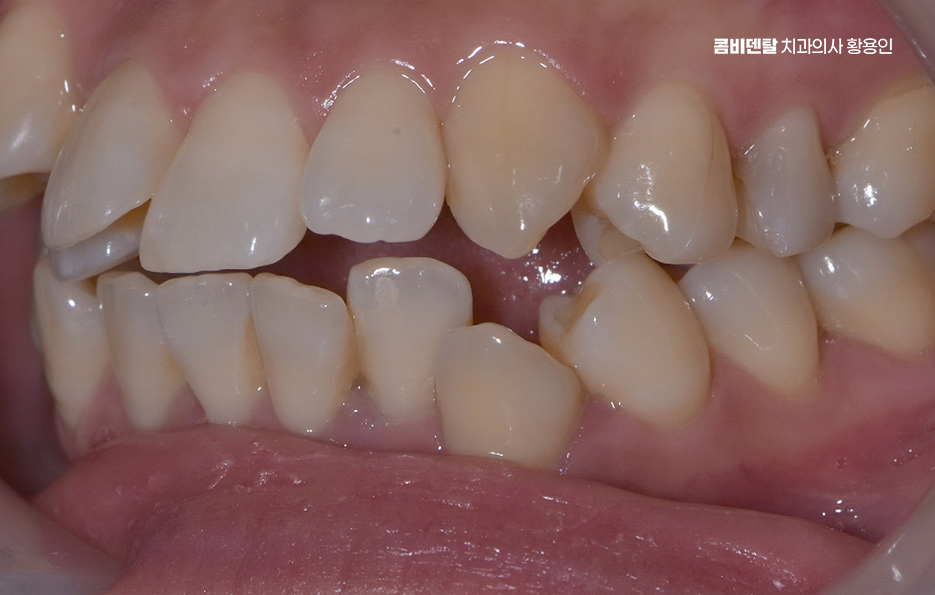

예를 들어 송곳니가 제자리를 찾지 못해 앞으로 튀어나와 있거나, 소구치가 비틀어져 있으면 그 힘이 앞니로 전달되면서 앞니가 서로 겹치고 밀리는 형태가 되는데 즉, 보이는 앞니가 문제처럼 보일 뿐, 실은 그 뿌리를 뒤에서 밀어내는 힘들이 원인이 될 수 있기 때문에 앞니만 간단히 밀어넣는 식의 교정은 일시적인 변화만 줄 수 있고 전체 치열을 다 잡아줘야 안정적인 결과를 만들 수 있었어요.

전체적인 부정교합을 교정하려면 먼저 교합 상태, 즉 위아래 치아가 어떻게 맞물리는지를 확인해야 하는데 위턱과 아래턱이 서로 자연스럽게 맞물리지 않고, 삐뚤거나 앞니가 부딪치거나, 아래턱이 더 튀어나와 있는 경우가 많이 있었어요

또 턱의 비대칭이나 턱관절 이상이 있는지까지 함께 체크해야 하는데 이런 부분을 모두 포함해서 앞니 틀어짐 교정 치료 계획이 세워져야 하며 얼굴의 중심선과 턱의 위치까지 고려한 계획이 필요한 거예요.

앞니 틀어짐 교정 앞니가 많이 틀어져 있는 경우에 발치가 필요한 경우도 있는데 공간이 부족한 상태에서 억지로 밀어넣으면 교정은 되지만 얼굴형이 부자연스러워지거나, 입이 오히려 더 튀어나와 보일 수 있어서 위아래 소구치를 발치해서 공간을 만들고, 그 공간을 활용해 전체 치아를 재배열하는 방식이 흔히 사용되고 있어요

물론 발치 여부는 개인의 얼굴형, 입술 돌출 정도, 잇몸뼈 두께 등 다양한 요소를 고려해서 결정하는 것이며 비발치적인 방법인 치간삭제, 어금니 후방이동, 악궁확장과 같은 방법으로 치아 이동 공간을 확보하여 비발치 치아교정이 가능한 경우도 있었어요